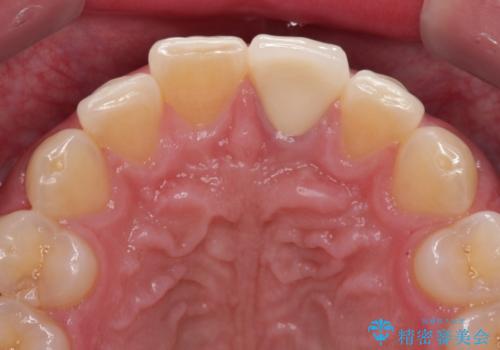

- 神経を取り除いたことで変色した前歯を気にして来院された患者様です。

根管治療はやり直さずに、ファイバーポストを使用した土台を植立してオールセラミッククラウンにて補綴することとしました。

神経を取り除いた歯は時間とともに変色してきます。

クリーニングやホワイトニングでは改善できないため、オールセラミッククラウンなどによる補綴治療が必要となります。